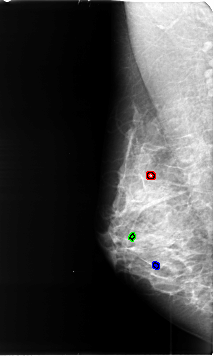

B_3452_1.RIGHT_MLO

RIGHT_MLO LINES 4624 PIXELS_PER_LINE 2776 BITS_PER_PIXEL 12 RESOLUTION 50 OVERLAY

FILE: B_3452_1.RIGHT_MLO.OVERLAY

TOTAL_ABNORMALITIES 3

ABNORMALITY 1

LESION_TYPE CALCIFICATION TYPE ROUND_AND_REGULAR-LUCENT_CENTERED DISTRIBUTION N/A

ASSESSMENT 2

SUBTLETY 3

PATHOLOGY BENIGN_WITHOUT_CALLBACK

ABNORMALITY 2

ABNORMALITY 3